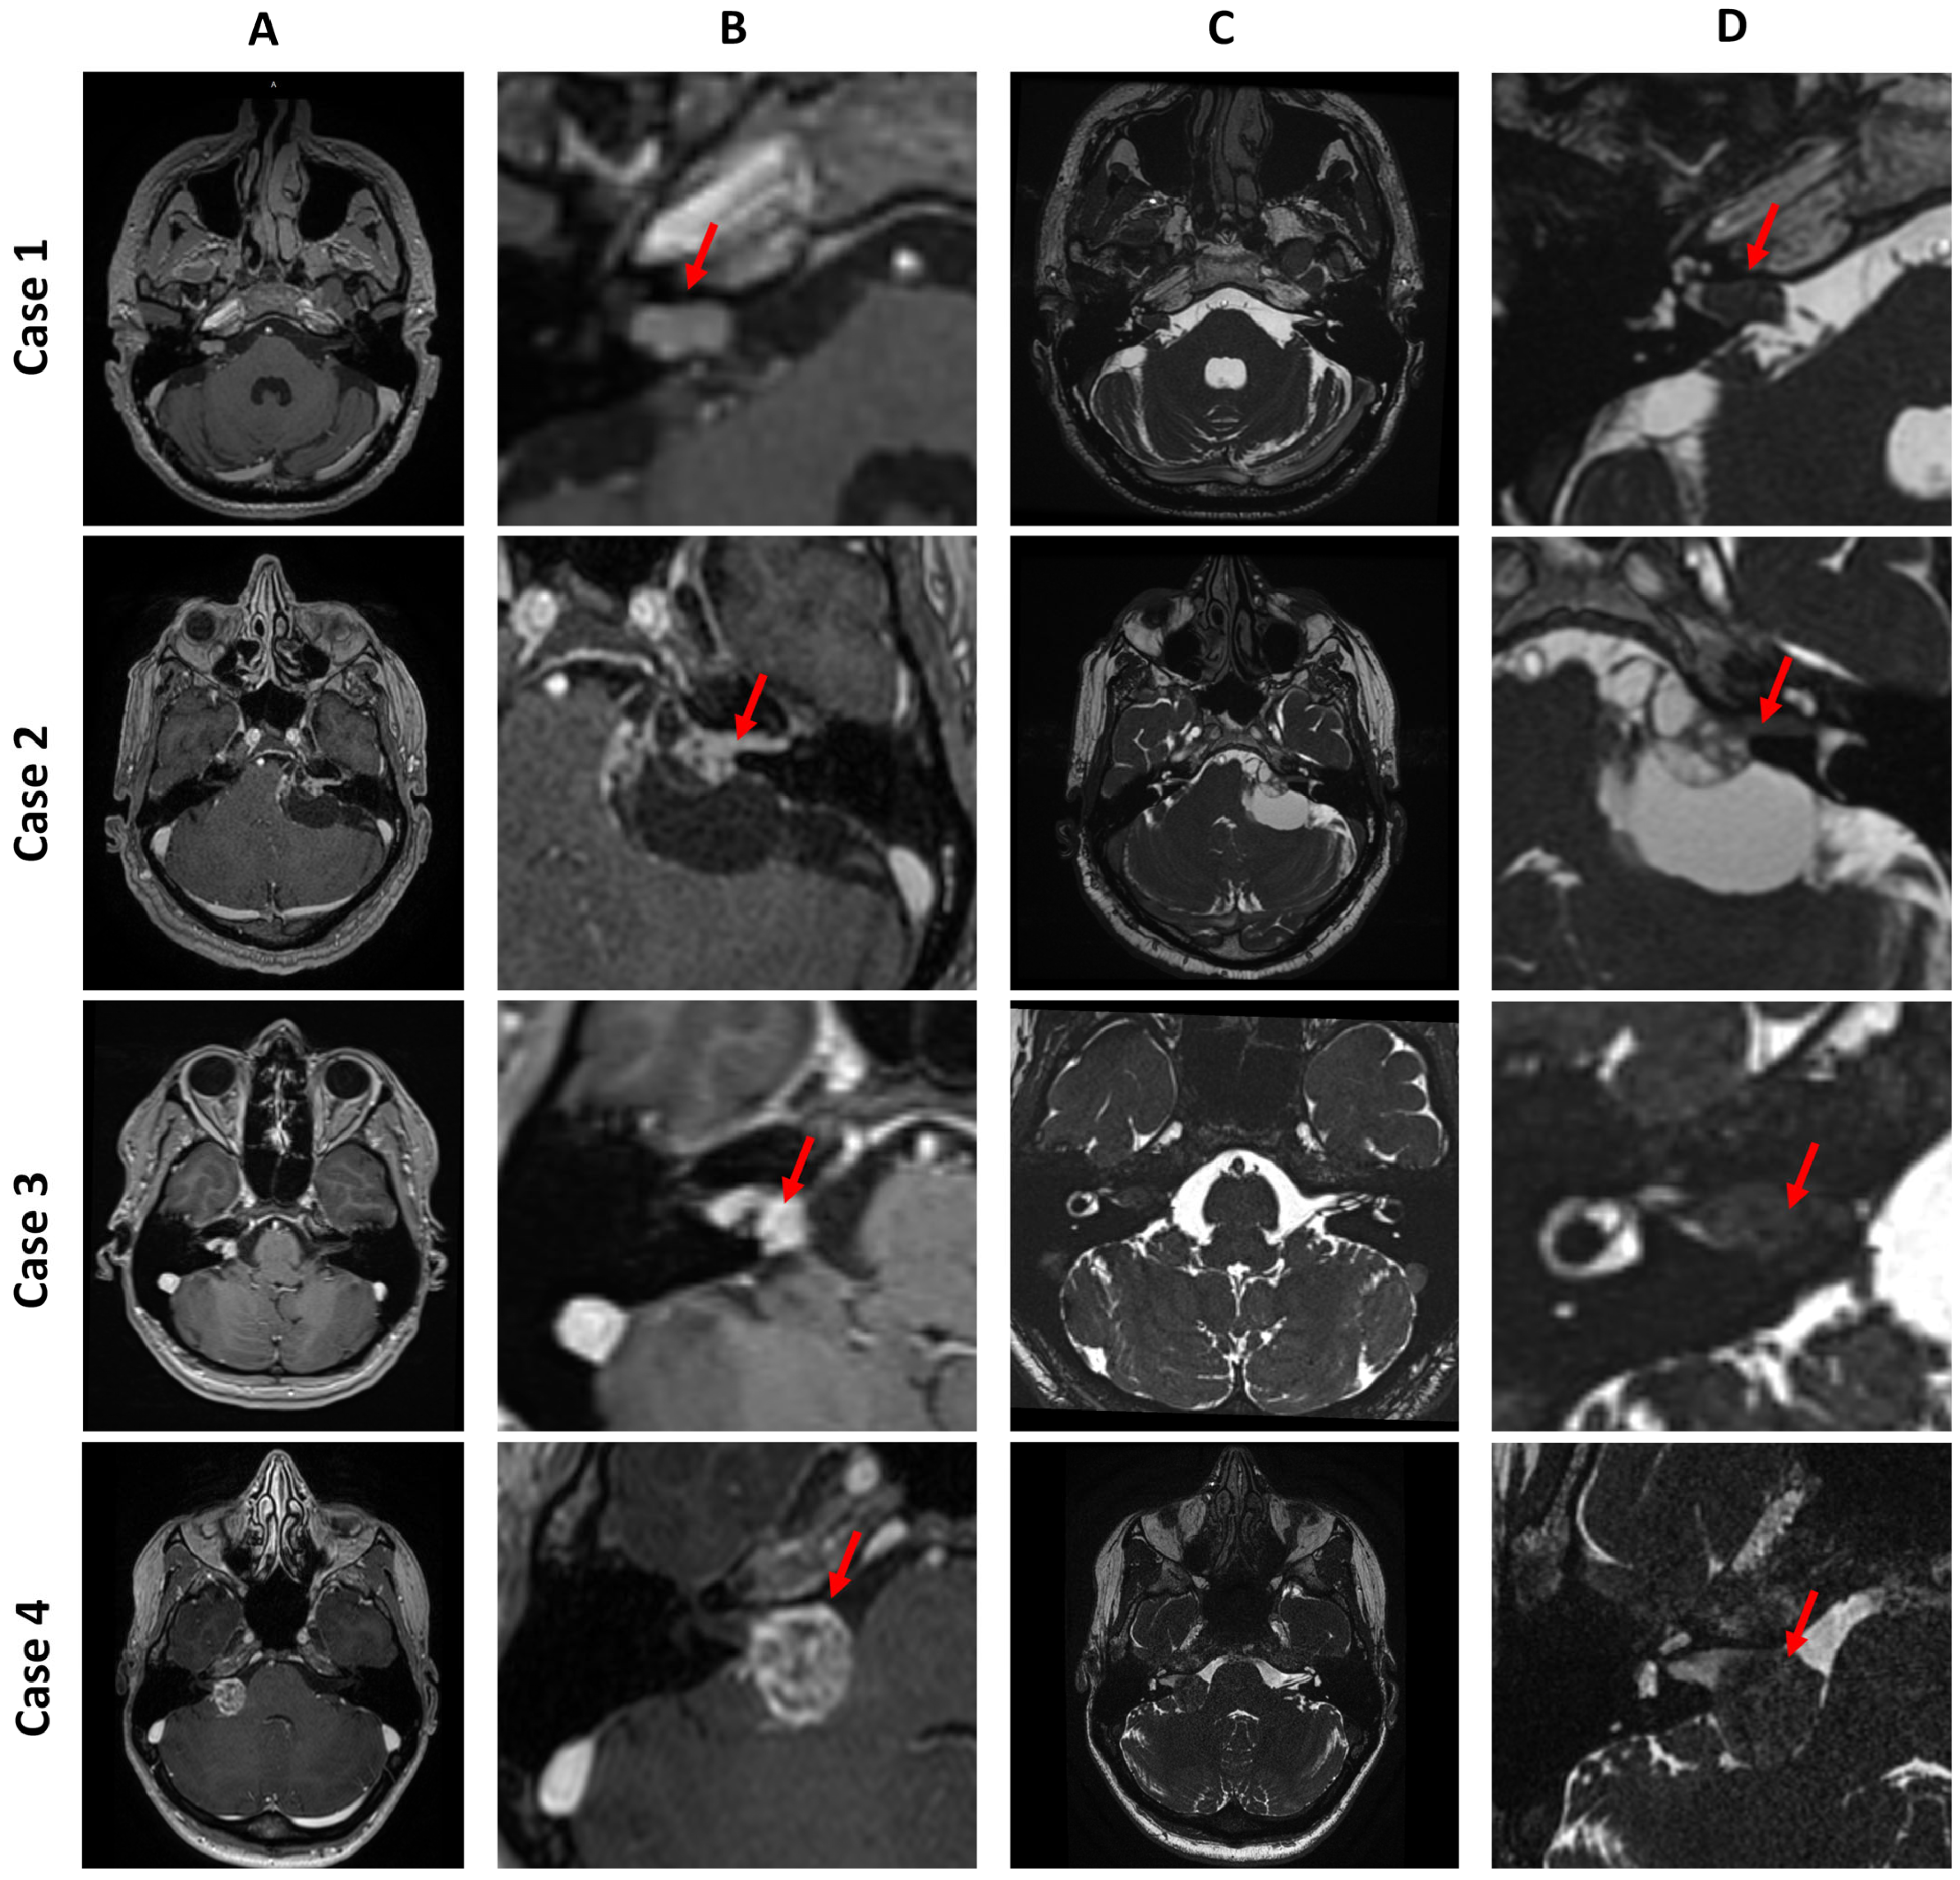

• Case 1 is a Koos I intracanalicular vestibular schwannoma in the right internal acoustic meatus with CSF cap separating the tumor from the cochlea.

• Case 2 is a Koos IV vestibular schwannoma with a cystic component in the left cerebellopontine angle, causing brainstem displacement.

• Case 3 is a Koos II vestibular schwannoma occupying the fundus of the right internal acoustic meatus and protruding into the cerebellopontine angle.

• Case 4 is a Koos III vestibular schwannoma present in the right cerebellopontine angle cistern, occupying less than half of the internal acoustic meatus.

Figure 5. Four cases of vestibular schwannoma presented in four consecutive rows. Column (A) and column (B) show a general and detailed view of T1-weighted images with contrast enhancement. Column (C) and column (D) show a general and detailed view of T2-weighted images. The red arrow points to the tumor.